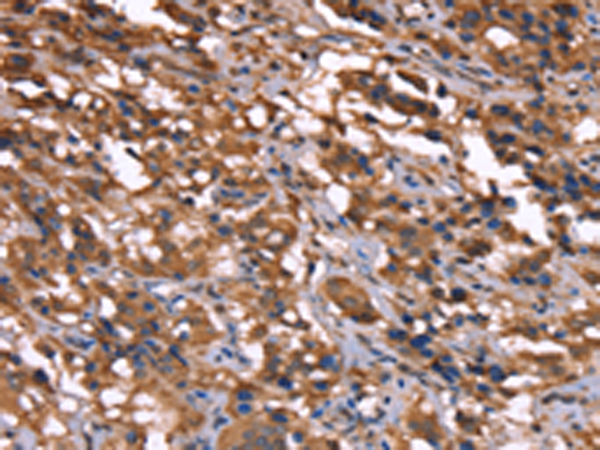

The image is immunohistochemistry of paraffin-embedded Human colon cancer tissue using P04919(GREB1 Antibody) at dilution 1/40. (Original magnification: ×200) |

The image is immunohistochemistry of paraffin-embedded Human thyroid cancer tissue using P04919(GREB1 Antibody) at dilution 1/40. (Original magnification: ×200) |